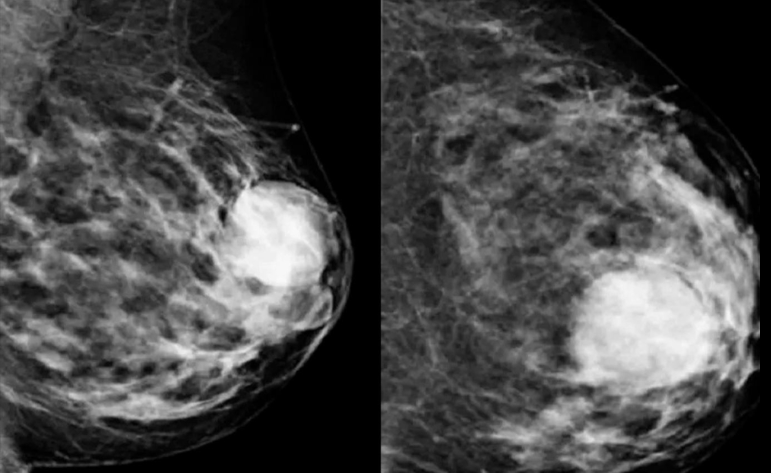

Πολλά από αυτά τα σημάδια μπορεί να οφείλονται και σε καλοήθεις (μη καρκινικές) παθήσεις του μαστού. Τα συμπτώματα αυτών των καταστάσεων μπορεί να περιλαμβάνουν ογκίδια, πόνο ή έκκριση από τις θηλές. Κάποιες καλοήθεις καταστάσεις μπορεί να φανούν σε μαστογραφία.

Αν παρατηρήσετε κάποιο ογκίδιο ή άλλη αλλαγή στον μαστό σας, κλείστε ραντεβού με γιατρό ή άλλο επαγγελματία υγείας. Αναφέρετε οποιεσδήποτε αλλαγές στους μαστούς σας, ακόμα κι αν μια πρόσφατη μαστογραφία έδειξε ότι δεν υπάρχει καρκίνος.

Ο καρκίνος του μαστού παραμένει μια από τις σημαντικότερες προκλήσεις υγείας που αντιμετωπίζουν εκατομμύρια άνθρωποι παγκοσμίως, κυρίως γυναίκες. Ωστόσο, οι ιατρικές εξελίξεις, η αυξημένη ενημέρωση και η έγκαιρη διάγνωση έχουν βελτιώσει σημαντικά τα ποσοστά επιβίωσης και την ποιότητα ζωής πολλών ανθρώπων. Η κατανόηση του καρκίνου του μαστού — των συμπτωμάτων, των αιτιών και των σταδίων του — είναι καθοριστική για να αποκτήσουμε τον έλεγχο της υγείας μας. Οι τακτικοί αυτοεξετάσεις, οι προληπτικές μαστογραφίες και οι ιατρικοί έλεγχοι αποτελούν τη βάση της έγκαιρης διάγνωσης. Η αναγνώριση του καρκίνου σε πρώιμο στάδιο σημαίνει συχνά απλούστερη θεραπεία και καλύτερη πρόγνωση.